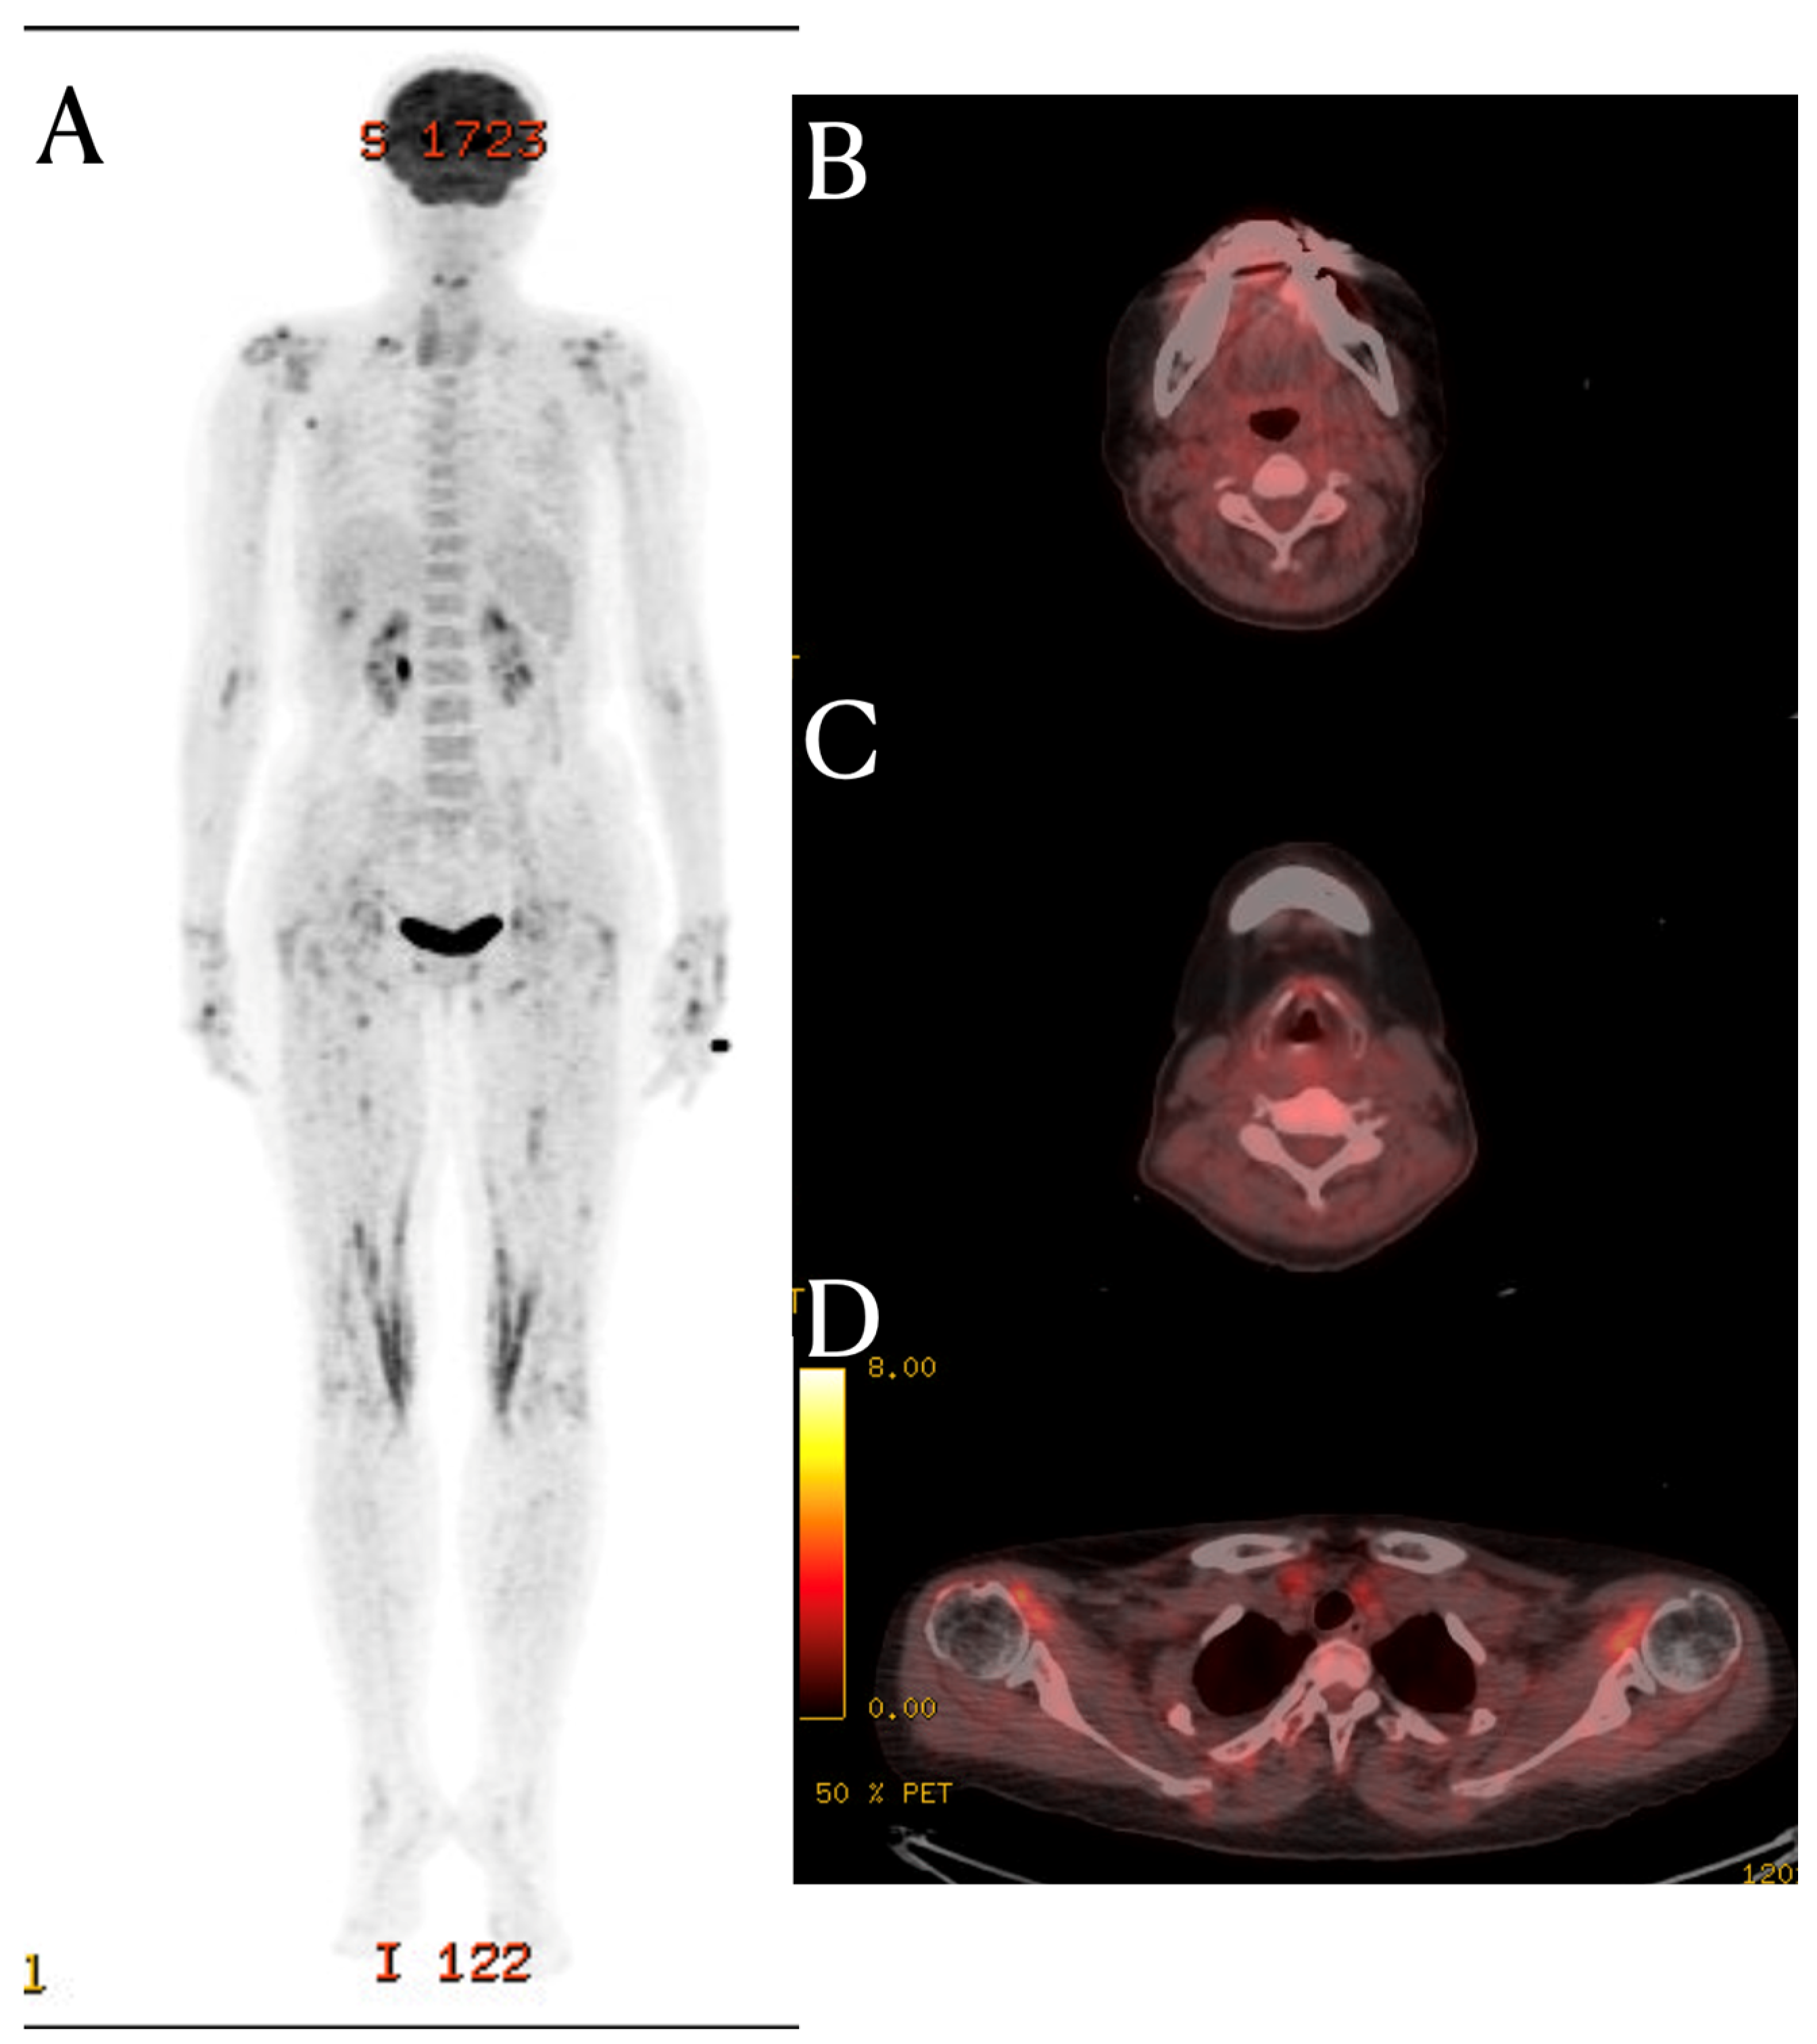

A C-spine MRI was performed, revealing evidence of degenerative spondylosis at the C5-6 level (Figure 1). The findings suggested potential causes for the patient’s pain, as considered by another hospital. However, the MRI also showed signal changes in the prevertebral area and the intermuscular fascia of the posterior neck area. While signal changes in such soft tissues are commonly observed in cases of traumatic injury, they are not frequently seen in cases of non-traumatic degeneration [3]. Inflammation in soft tissues is often observed in autoimmune diseases such as rheumatologic diseases and vasculitis [4]. SLE activates immune cells through nuclear self-antigens, inducing inflammation in connective tissues such as cartilage, ligaments, muscles, skin, blood vessels, and other soft tissues. The fascia is a tissue that encompasses these connective tissues, including interosseous membranes, tendons, entheses, epimysium, and vessels.

The fat-suppressed T2-weighted image is a sensitive MRI sequence for confirming active enthesitis [5]. Furthermore, the intermuscular fascia, which contains a significant amount of fatty tissue, may not display abnormalities in T2-weighted images without fat suppression. In this patient, the T2-weighted images did not reveal any specific findings in the posterior cervical area, but significant signal changes were observed in the fat-suppressed T2-weighted view. Therefor, for diffential diagnosis, the fat suppression view provides valuable information. Similarly, this case demonstrates the importance of fat-suppressed T2-weighted images in identifying structural changes in fascia, which are frequently affected in systemic inflammatory diseases.

Figure 1. Cervical spine MRI. In the T2-weighted sagittal image, mild edema and high signal changes in the prevertebral soft tissue (arrow) are found (AC). Notably, on the fat suppression T2-weighted image, additional findings of high signal intensity in the posterior neck fascia (arrowhead) are observed (B).